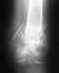

Re: закритий двухкисточковыйп ерелом косточек правой голени с смещением,и частичное повреждение дистального межголеньего синдесмоза с подвывихом ступнин

Проблем больших не видно. Нужно разрабатывать движения. В качестве образца - здоровая нога. Надо именно разрабатывать. Частичная нагрузка возможна. Будете ее увеличивать по мере спадения отека.